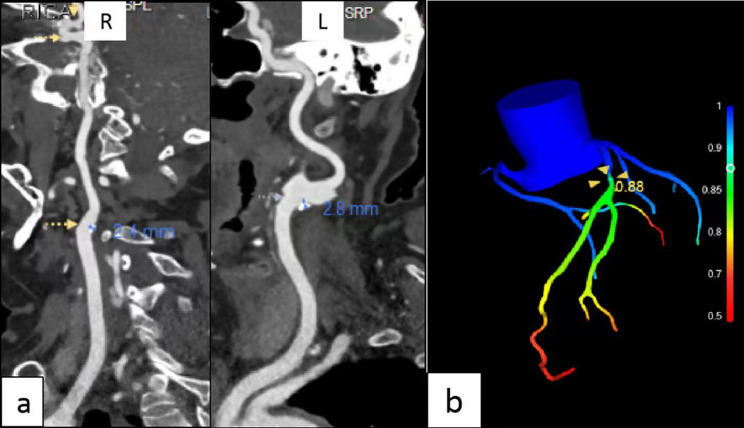

Background: The study aimed to investigate the correlation of carotid plaque and peripheral carotid adipose tissue (PCAT) characteristics with coronary computed tomography-derived fractional flow reserve (CT-FFR) values.

Methods: Data of 136 patients who underwent head and neck computed tomography angiography (CTA) followed by coronary CTA were retrospectively reviewed. Based on their CT-FFR values, they were divided into CT-FFR ≤ 0.8 and CT-FFR > 0.8 groups. The patients' baseline data, carotid plaque and PCAT characteristics were collected. Univariate analysis and multivariate logistic regression were employed to identify differences between groups.

Results: Univariate analysis indicated a statistical differences in carotid plaque thickness, plaque area, plaque load, the carotid plaque Crouse score, minimum plaque density, and net enhancement value of PCAT of patients (P < 0.05). Based on this, multivariate logistic regression analysis demonstrated that carotid plaque thickness (odds ratio (OR) = 0.553; 95% confidence interval (CI) = 0.360-0.847), the carotid plaque Crouse score (OR = 0.653; 95% CI = 0.514-0.830), and net enhancement value of PCAT (OR = 0.820; 95% CI = 0.730-0.919) were independent predictors of the diagnosis of CT-FFR ≤ 0.8. Furthermore, receiver operating characteristic curve analysis showed that the area under the curve of plaque thickness, the carotid plaque Crouse score, and net enhancement value of PCAT for the diagnosis of CT-FFR ≤ 0.8 were 0.816, 0.843, and 0.836, respectively.

Conclusion: Carotid plaque thickness, the carotid plaque Crouse score, and net enhancement value of PCAT are independent related indicators of CT-FFR ≤ 0.8, which can be simultaneously clarified by head and neck CTA alone, as well as the severity of coronary atherosclerosis.